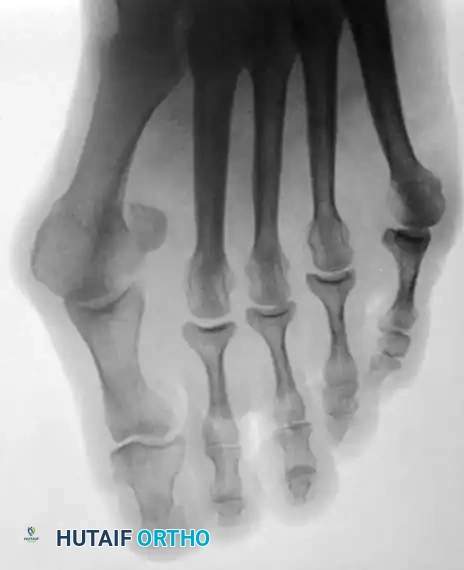

In contemporary orthopedic practice, a bunionette is frequently observed as part of a broader forefoot pathology, most notably the splay foot deformity combined with hallux valgus. The etiology is multifactorial. The head of the fifth metatarsal may be congenitally or traumatically enlarged (Type I deformity). Alternatively, the diaphysis may be angulated laterally (Type II deformity), or there may be a widened fourth-fifth intermetatarsal angle (Type III deformity), making the fifth metatarsal head excessively prominent.

Fig. 80-30 A and B, Bunionette with metatarsus quintus valgus and fifth toe varus.

Fig. 80-31 Bunionette–hallux valgus–splay foot complex. Note lateral angulation of shaft of fifth metatarsal at distal third (arrows).